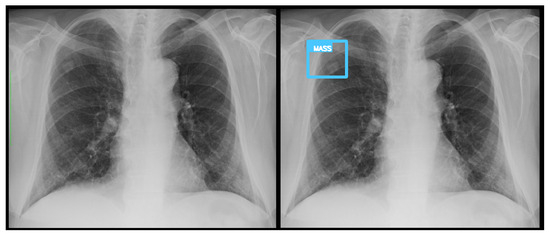

3.3. Error Analysis

An analysis of the algorithm’s false negatives revealed a nuanced performance profile, where a specific miss did not always equate to a complete system failure. Across the board, a substantial number of cases with a false negative for a particular pathology were nevertheless correctly identified as abnormal by the general “yes-finding” classifier or had other co-occurring true positive pathologies. For example, out of 38 false negatives for opacity, the algorithm correctly identified the exam as abnormal in 25 cases. In many instances of a missed finding, the algorithm successfully detected other pathologies within the same study. Misclassification was another notable source of error, where an existing pathology was detected but incorrectly labeled, such as opacities being predicted as masses or nodules (Figure 4). Radiologist review of these false-negative cases frequently noted findings that were “subtle,” “small,” “doubtful,” “seen on lateral image only,” or “non-specific.” In other cases, the algorithm correctly identified a more critical finding, like a large pleural effusion, while missing a secondary, less significant pathology (Figure 3). Figure 9, Figure 10 and Figure 11 illustrate false negative cases for opacity, pneumothorax, and nodule, respectively. This highlights the inherent limitations and inevitable failures of this kind of system.

Figure 5. A true positive example of opacity and consolidation (left) and its contour line generated image (right).